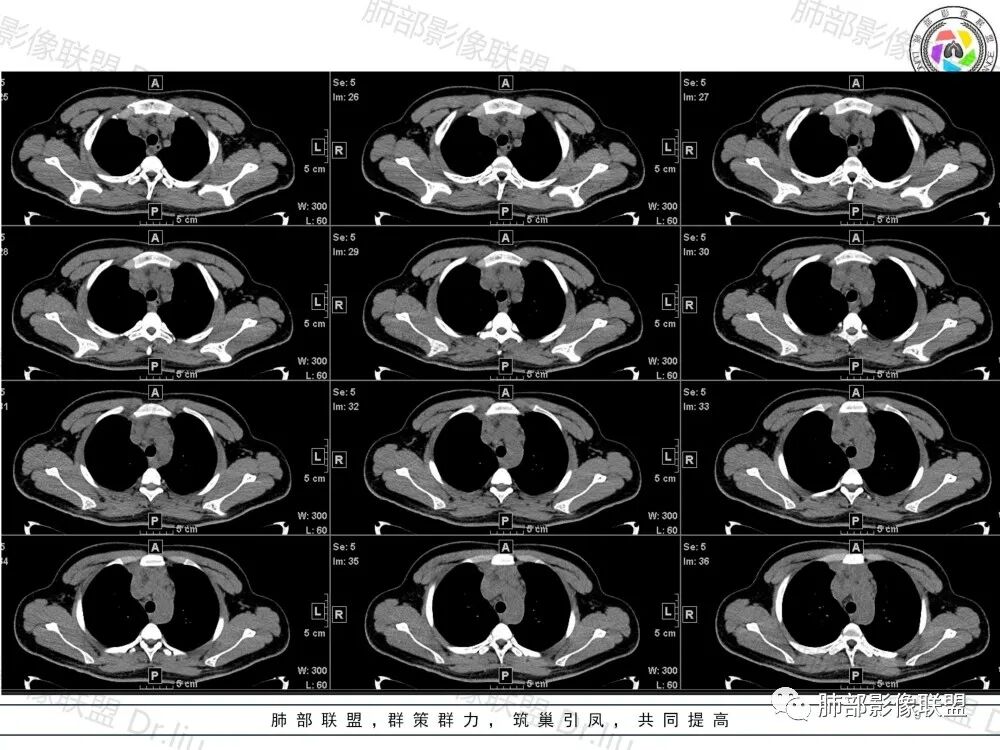

1、临床特点:19岁男性,发现双肺结节,实验室检查无特殊。

2、影像特点:两肺可见多发大小不一的结节影,部分结节周围可见晕征,部分结节沿着支气管血管束分布,部分位于胸膜下。前纵隔内可见多发结节样软组织密度影,边界不清,部分病灶融合倾向,其脂肪间隙显示模糊。由于腹腔层面少,未能确定腹腔内有无增大淋巴结,需要连续层面追踪观察。